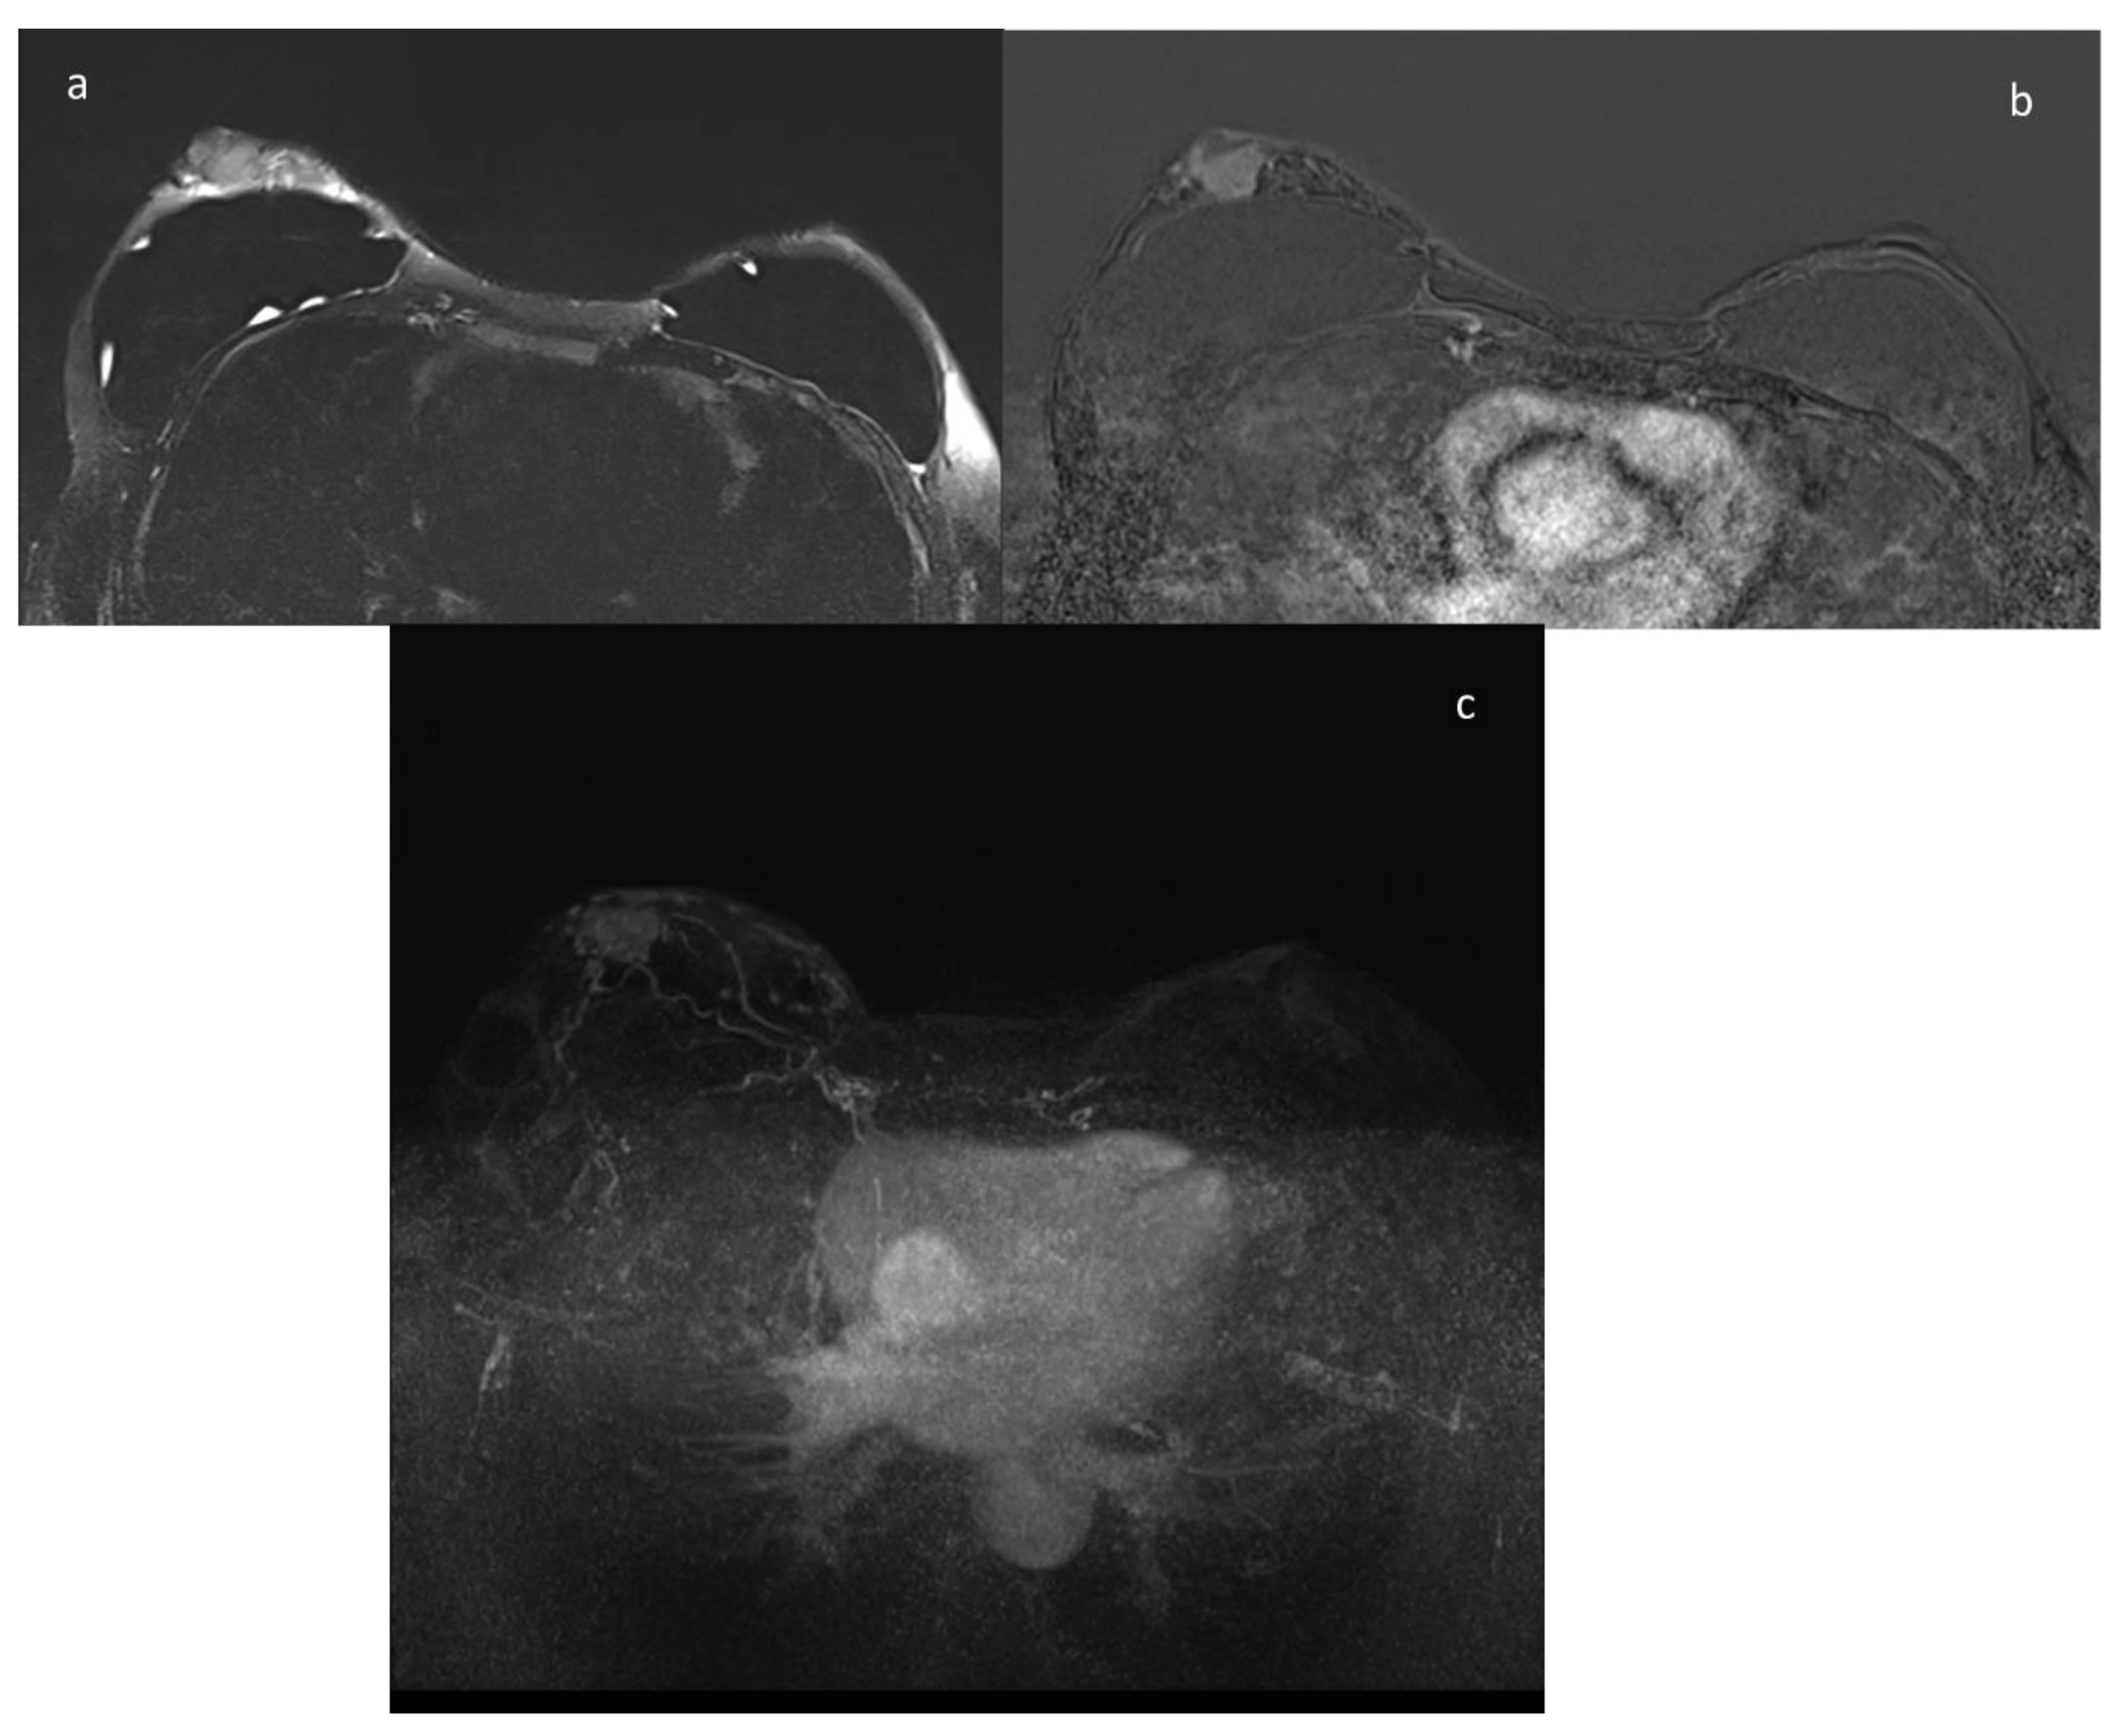

9. ce-MRI

- Mann, R.M.; Cho, N.; Moy, L. Breast MRI: State of the Art. Radiology 2019, 292, 520–536. [Google Scholar] [CrossRef] [PubMed]

- Pinker, K.; Helbich, T.H.; Morris, E.A. The potential of multiparametric MRI of the breast. Br. J. Radiol. 2017, 90, 20160715, Erratum in 2017, 90, 20160715e. [Google Scholar] [CrossRef] [PubMed]